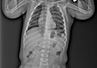

47-річна львів’янка Людмила С. не мала скарг на роботу легень, вона рідко хворіла, не курить. Та під час планового обстеження у поліклініці на оглядовій рентгенографії лікарі помітили патологічні зміни. Комп’ютерна томографія підтвердила – у лівій легені є пухлина. У львівській лікарні св. Луки жінці вперше зробили торакоскопічну операцію з видалення пухлини.

Результати обстеження спершу львів’янку шокували, бо вона не мала жодних скарг. З результатами обстеження звернулася до спеціалістів лікарні св. Луки. У медзакладі їй зробили КТ всього тіла, аби виключити поширення патологічних вогнищ на інші органи та тканини, і паралельно – відеобронхоскопію, щоб оцінити стан бронхіального дерева, повідомили у лікарні.

Новоутвір однозначно треба було видаляти. Торакальні хірурги вирішили прооперувати пацієнтку найменш травматичним способом – торакоскопічно, видалили пухлину через три проколи завдовжки по 2 см. Звичне втручання проводять з розкриттям грудної клітки і розріз становить 15-20 см. Під час операції хірурги видалили нижню частку лівої легені разом з пухлиною та групою лімфатичних вузлів.

Операція з видалення новоутвору легені тривала чотири години та минула успішно. Зараз лікарі та пацієнтка очікують на результати гістології. Якщо пухлина виявиться злоякісною, то жінціі призначать хіміотерапію.